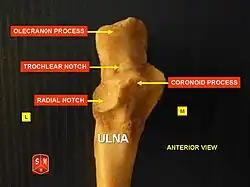

Posterior end of the ulna, with the olecranon labelled at top. | |

The olecranon (/oʊˈlɛkrənɒn/, from Greek olene 'elbow' and kranon 'head'), is a large, thick, curved bony process on the proximal, posterior end of the ulna. It forms the protruding part of the elbow and is opposite to the cubital fossa or elbow pit (trochlear notch). The olecranon serves as a lever for the extensor muscles that straighten the elbow joint.

Structure

The olecranon is situated at the proximal end of the ulna, one of the two bones in the forearm.[1] When the hand faces forward (supination) the olecranon faces towards the back (posteriorly).

It is bent forward at the summit so as to present a prominent lip which is received into the olecranon fossa of the humerus during extension of the forearm.[2][3]

Its base is contracted where it joins the body and the narrowest part of the upper end of the ulna.

Its posterior surface, directed backward, is triangular, smooth, subcutaneous, and covered by a bursa.

Its superior surface is of quadrilateral form, marked behind by a rough impression for the insertion of the triceps brachii; and in front, near the margin, by a slight transverse groove for the attachment of part of the posterior ligament of the elbow-joint.

Its anterior surface is smooth, concave, and forms the upper part of the semilunar notch.

Its borders present continuations of the groove on the margin of the superior surface; they serve for the attachment of ligaments, viz., the back part of the ulnar collateral ligament medially, and the posterior ligament laterally.

From the medial border a part of the flexor carpi ulnaris arises; while to the lateral border the anconeus muscle is attached.